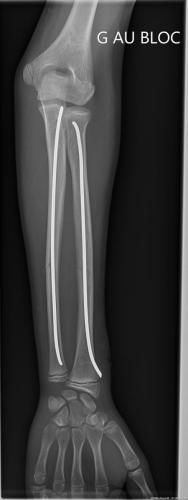

Fracture de l’avant-bras 31 mars 202519 mars 2024 par Damien Traitement Traitement orthopédique Embrochage centro-médullaire